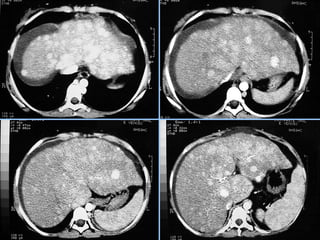

Hemangioma

 S/C              Fase art.

 Fase portal      Fase tardia